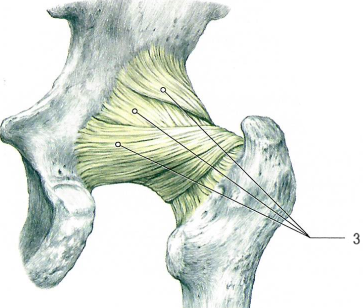

Тазобедренный сустав по строению простой, по форме шаровидный (чашеобразный), по функции многоосный.

Сустав образован полулунной поверхностью вертлужной впадины тазовой кости (имеет вертлужную губу[2]) и головкой бедренной кости.

В суставе возможны сгибание и разгибание, отведение и приведение, пронация и супинация, круговые движения бедра.

Связки, укрепляющие тазобедренный сустав.